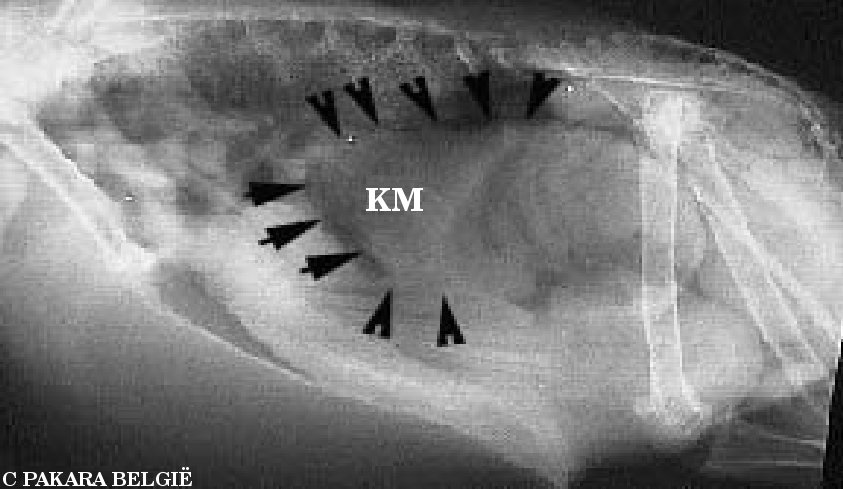

Röntgenstralen zijn een belangrijke hulp bij het vaststellen van deze ziekte.

De verschillende magen zullen een vergroting laten zien, die men met

röntgenstralen kan laten zien door barium. Deze stof laat het toe om de

verschillende structuren van het spijsverteringsstelsel duidelijk te laten zien.

Het laat ook zien of het stelsel normaal is, dit bepalen ze door te kijken

hoelang het barium nodig heeft om volledig te passeren.

Hetgeen dat nu volgt is zo een röntgenonderzoek. Maar eerst nog een beetje

uitleg bij de foto's. De vogel ligt op zijn rechterkant met de kop naar links.

De volgende geeft de belangrijkste delen weer

LZ = luchtzak

PV = kliermaag

M = milt